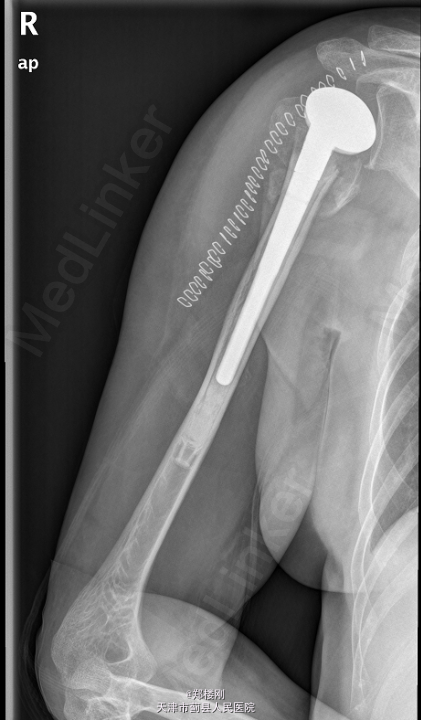

右肱骨近端骨折 全麻下行右半肩关节置换术

右上肢切口处敷料包扎固定妥,切口对合良好,切缘干燥,无明显红肿渗出,无明显感染征象,末梢手指活动、血循、感觉可。